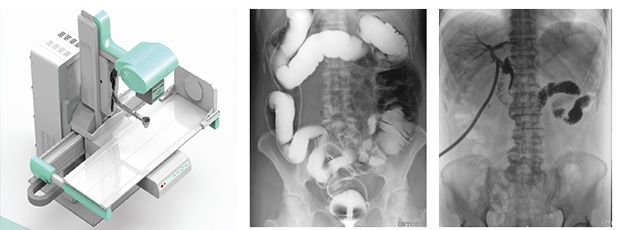

隨著現(xiàn)代醫(yī)療技術(shù)快速發(fā)展,傳統(tǒng)的X射線技術(shù)實(shí)現(xiàn)數(shù)字化,出現(xiàn)了多功能DR。多功能DR采用數(shù)字影像平板探測器取代傳統(tǒng)膠片,直接捕獲X線影像,并轉(zhuǎn)化為高清晰數(shù)字圖像,對比傳統(tǒng)的間接影像設(shè)備,多功能DR可以直接將X射線轉(zhuǎn)化成圖像,成像更清晰,放射劑量更小。

多功能DR大大提高了普通放射設(shè)備準(zhǔn)確診斷的能力,為臨床創(chuàng)造了價(jià)值,它可以進(jìn)行全身各部位的拍片、透視和點(diǎn)片攝影。接下來小編給大家介紹一下這三種模式的區(qū)別。

點(diǎn)片攝影是在透視的條件下,對病變部位進(jìn)行可視化觀察,待發(fā)現(xiàn)疑似病變部位的時(shí)候進(jìn)行瞬間點(diǎn)片,從而能夠準(zhǔn)確獲取病變部位的高清影像用于臨床診斷,從而在一定程度上降低漏診誤診率。病人不動,通過選擇鍵由透視直接切換攝影的曝光過程。在透視過程中,保存一幅靜止的圖像。常用于消化道、膽系造影下的攝影等。它既可以觀察運(yùn)動器官的運(yùn)動功能,又能在有感興趣的圖像時(shí),對膠片曝光保留感興趣的圖像,便于進(jìn)一步診斷。